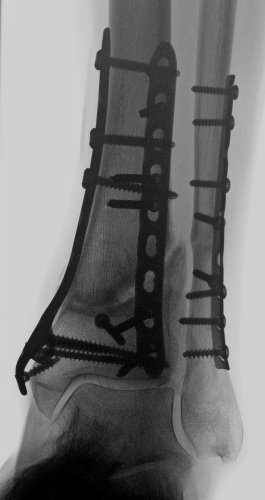

US_li_vorne.jpg

US_re_vorne.jpg

Ursächlich dafür ist - bezogen auf meinen ersten Bruch - mit Sicherheit auch die Positionierung der Schrauben. Auch wenn damals, 2011, alle Mediziner sagten, toll operiert (erstes Bild), so erlaube ich mir mittlerweile zu glauben, dass - siehe zweites Bild - in dem "Provinzkrankenhaus" in dem ich nach meinem Sturz gelandet bin, ein besserer Job gemacht wurde. Die Schraubenköpfe sitzen wesentlich bündiger am Knochen, daher spüre ich auch dort nichts reiben oder flipsen. Mag aber vielleicht jemand mit medizinischer Expertise erklären können, warum die beim ersten Mal so weit rausstanden (richtige Schraubenlänge nicht in der Werkzeugkiste?).